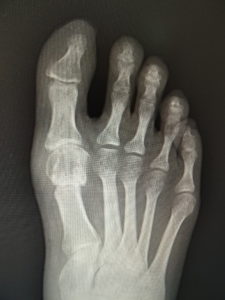

真田理事長による手術の様子。外反母趾|症例 (左から 手術前、手術後、ワイヤ抜去後)

61歳 女性